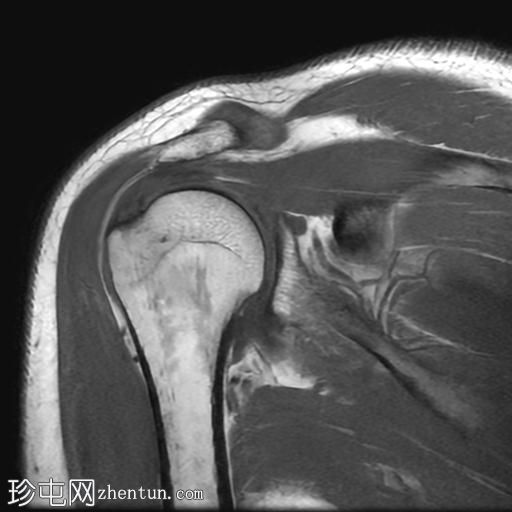

MRI

冠状位PD序列

冈上肌腱关节面中前部纤维可见部分撕裂(边缘撕裂),伴局部骨髓水肿。

冈上肌腱关键区纤维以及冈下肌腱均可见肌腱病。

肩锁关节周围可见轻度关节囊肥厚和退行性改变。

此外,肩峰下滑囊内可见积液。

MRI 检查结果符合冈上肌腱的典型边缘撕裂,也称为部分关节面肌腱撕脱。